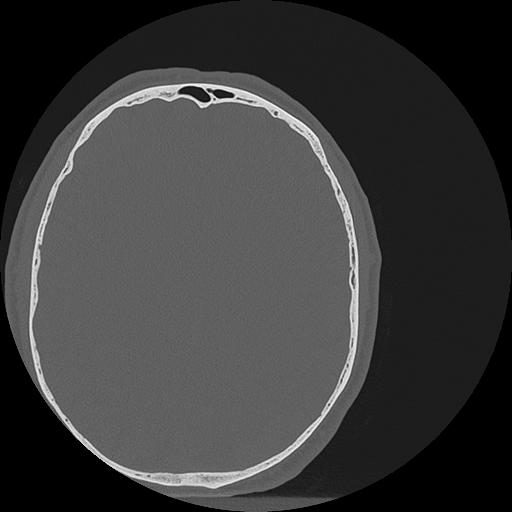

7 HUESO,,Vol,0.5,HUESO,,